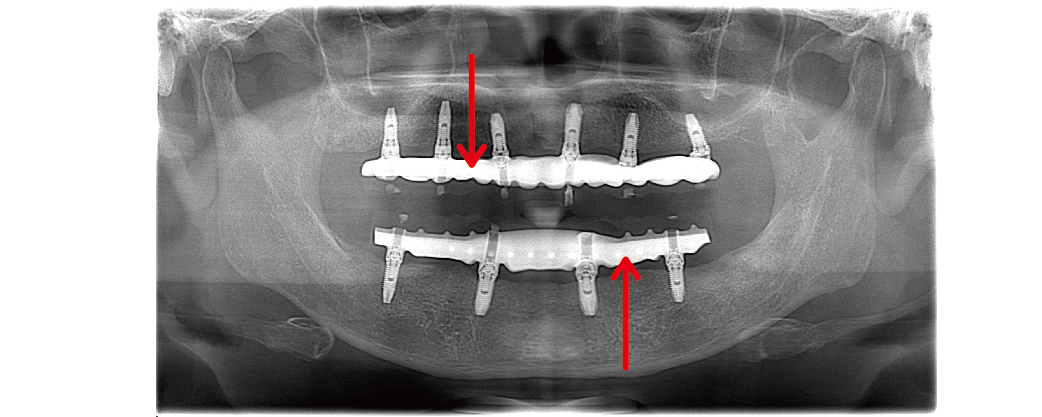

在環口式X光片檢查,可以看到上下顎的假牙內含金屬支架